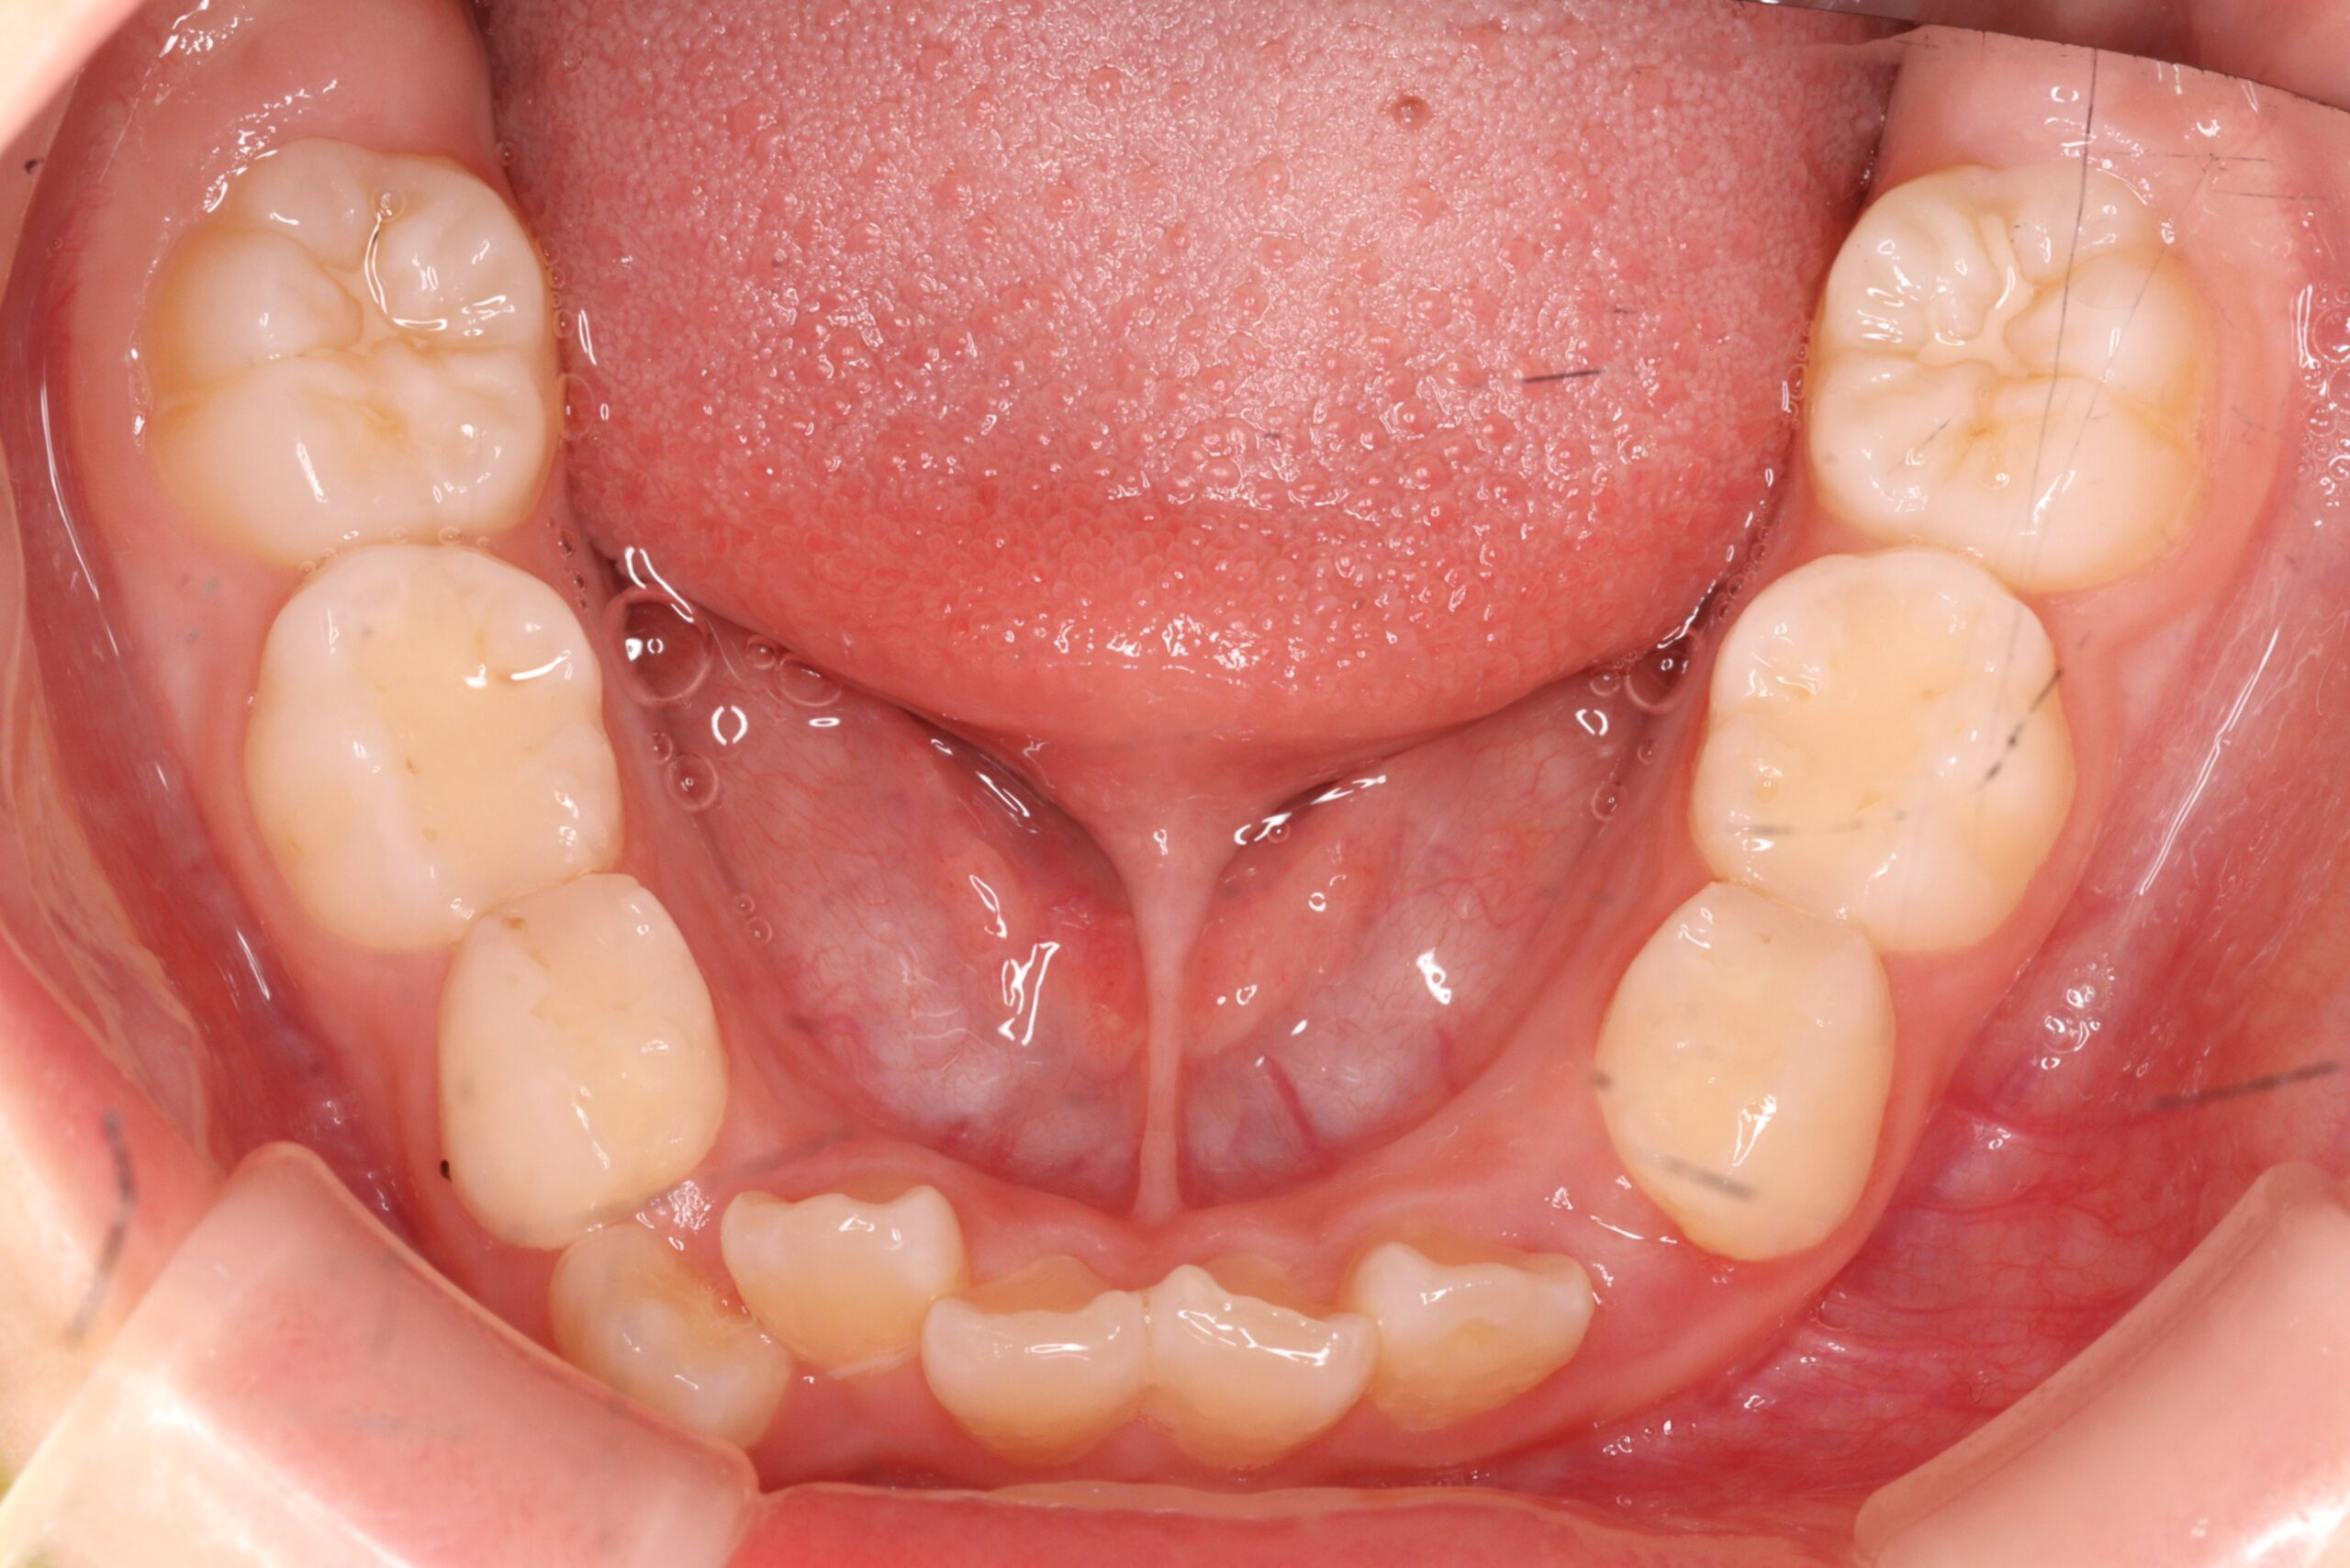

矯正術前:下顎

矯正術後:下顎